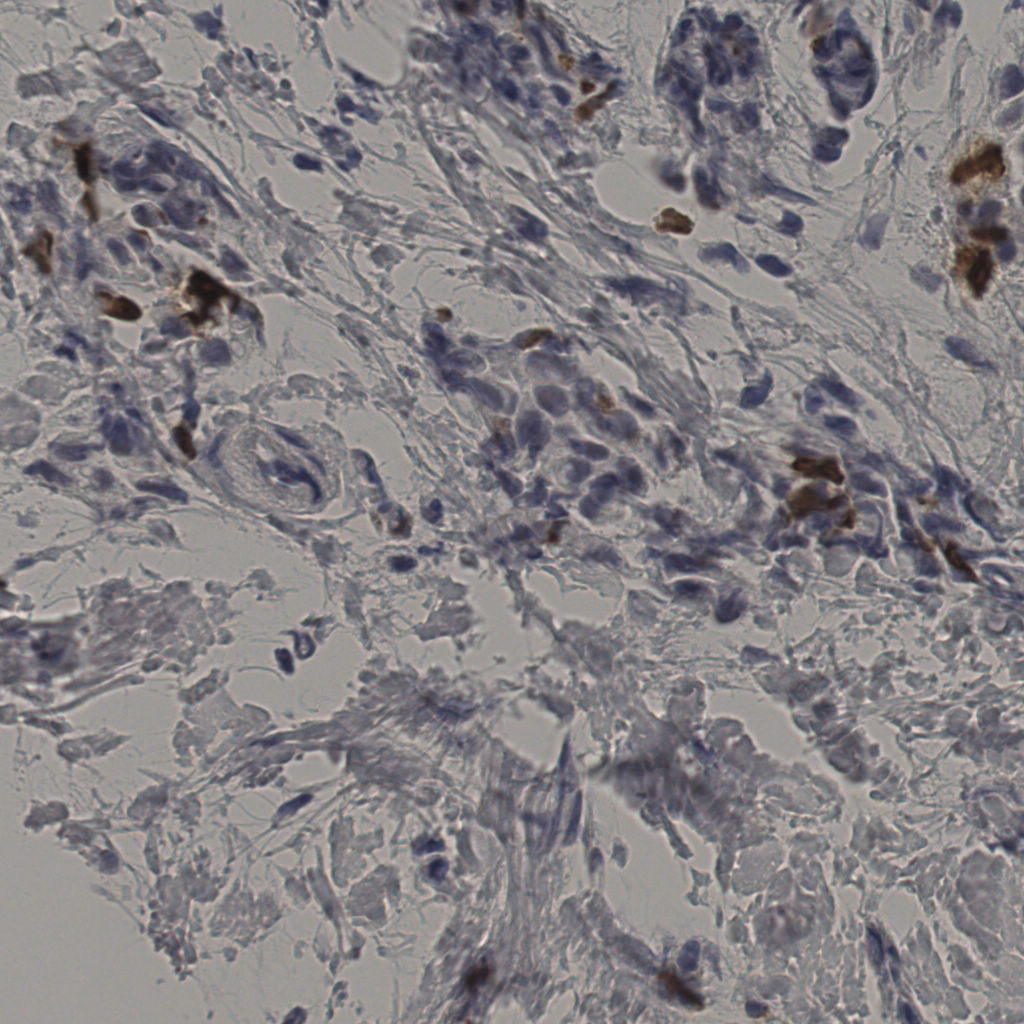

5.31%

Ki67 指数

阴 19502

阳 1093

切片统计

总切片

2970

有效

554

已标记

554

有效率

19%